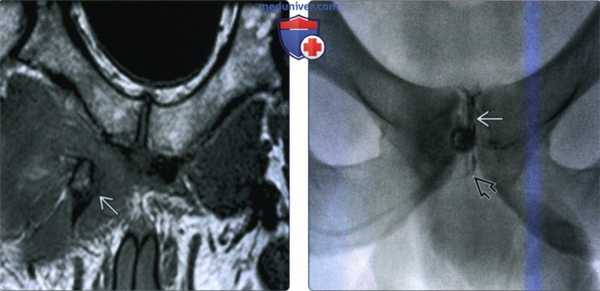

(Слева) МРТ Т1ВИ, косой коронарный срез: у профессионального баскетболиста после травмы при отведении бедра во время отскакивания визуализируется костный осколок, оторванный от бугорка лобковой кости. Костные отрывы длинной приводящей мышцы встречаются редко.

(Справа) На традиционной конусовидной артрографии перед введением глюкокортикостероидов определяется распространение контраста от лобкового симфиза в косом и нижнем направлении под местом начала длинной приводящей мышцы. Это признак вторичной расщелины, указывающий на частичный разрыв.в) Дифференциальная диагностика травмы приводящих мышцы бедра: